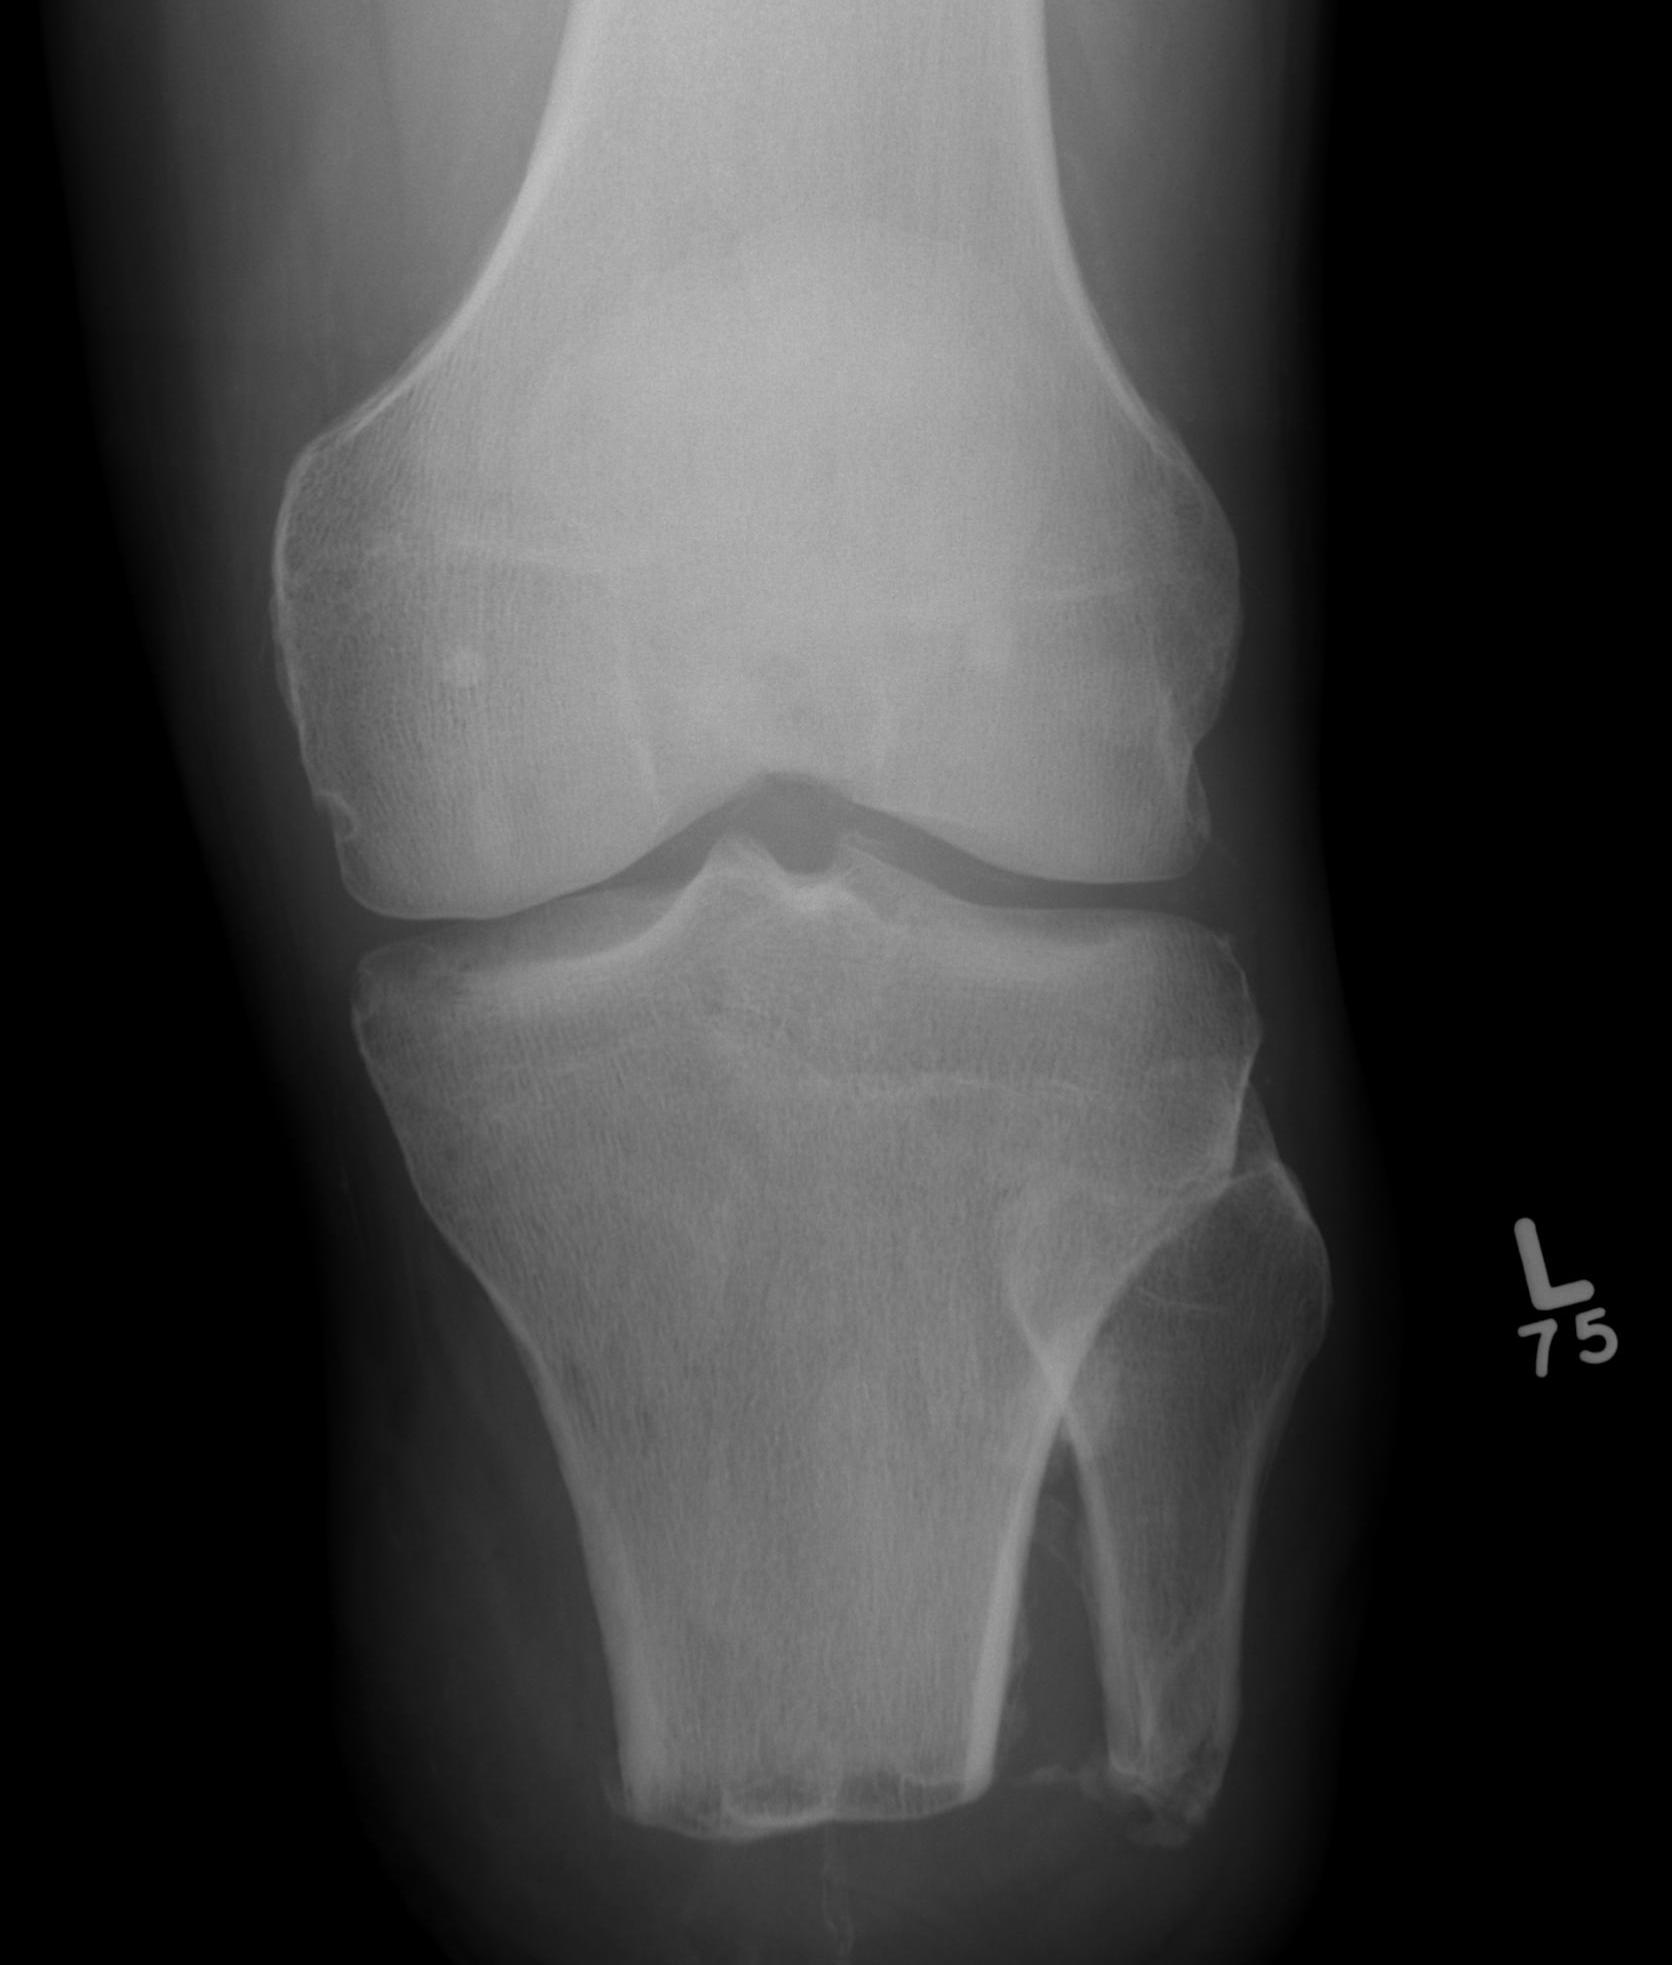

Trans-tibial amputation

www.boneschool.com/amputations-about-the-knee

Technique

Long posterior flap

- keep long tibial stump

- fibular cut 1 - 2 cm shorter

- gastrocnemius myodesis